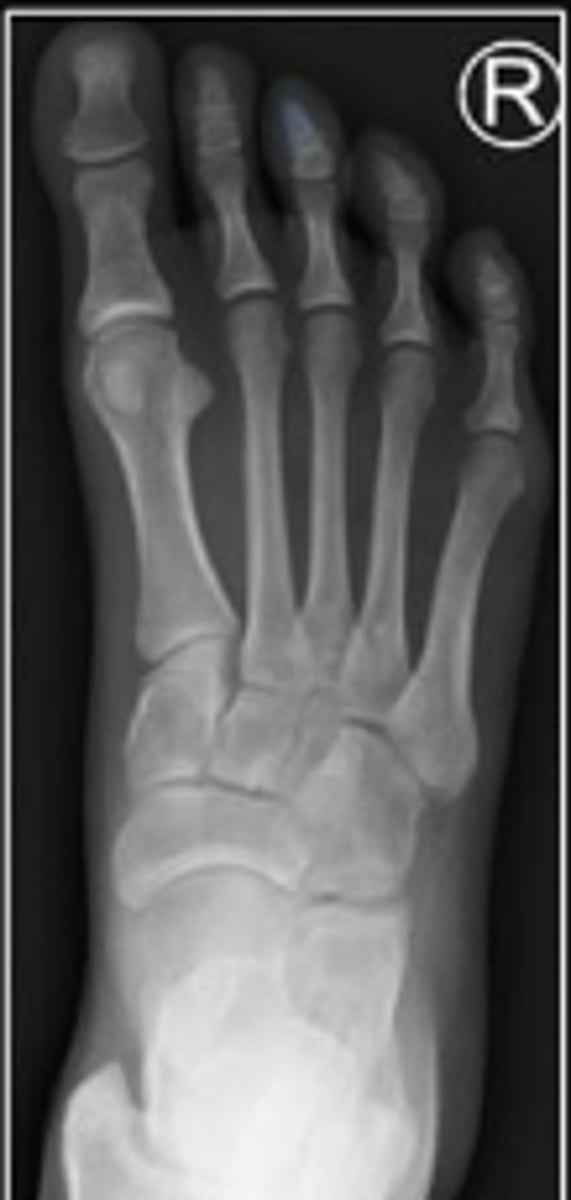

AP right foot

What is the name of the radiographic view?

2nd metatarsal of the right foot

What is outlined?

Cuboid of the right foot

What are the arrows pointing to?

Medial cuneiform of the right foot